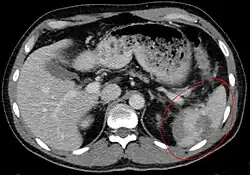

Die apparative Basisdiagnostik bei einem Verdacht auf Milzruptur ist die Sonographie der Bauchorgane. Der Nachweis von freier Flüssigkeit gelingt damit bereits bei kleinen Mengen, gröbere Parenchymverletzungen der Milz oder große subkapsuläre Hämatome lassen sich ebenfalls darstellen. Bei unauffälligem sonographischem Befund aber klinisch weiter bestehendem Verdacht muss die Untersuchung engmaschig wiederholt werden, um eine zweizeitige Ruptur oder ein zunehmendes Kapselhämatom nicht zu übersehen. Röntgenaufnahmen des Thorax und des Abdomens erbringen keine weiteren Hinweise auf das Vorliegen einer Milzruptur, werden aber zum Ausschluss weiterer Verletzungen (beispielsweise Rippenfrakturen mit Pneumothorax) durchgeführt. Bei stabilen Kreislaufverhältnissen kann eine Computertomographie des Abdomens genaueren Überblick über das Ausmaß der Milzverletzung geben. Die noch bis in die 1990er Jahre regelmäßig durchgeführte Peritoneallavage ist mittlerweile wegen ihrer hohen Fehlerquote nicht mehr gebräuchlich.